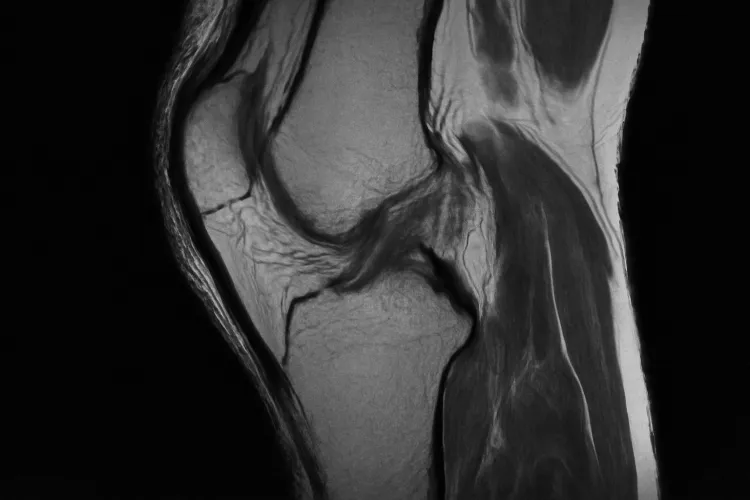

МРТ коленного сустава в Долгопрудном представляет собой современный и высокоинформативный метод исследования. Этот способ диагностики используется для оценки состояния ткани сустава, связок и хрящей. Благодаря магнитно-резонансной томографии, специалисты получают детализированные изображения, позволяющие выявлять различные патологии и нарушения функционирования колена. Метод безвреден для пациента, так как не требует использования ионизирующего излучения. Подобное исследование способствует быстрой и точной постановке диагноза, что, в свою очередь, позволяет начать лечение на ранних стадиях заболевания.

Томография коленного сустава предоставляет возможность диагностировать различные патологии и состояния. Основные проблемы, которые можно выявить с помощью этого метода:

- Повреждения менисков: точно оценить состояние боковых и медиальных менисков, определяя наличие разрывов или дегенеративных изменений.

- Патологии связок: повреждения передней и задней крестообразных связок, а также боковых связок колена.

- Артрит: признаки воспалительных изменений в суставной капсуле и наличие жидкости в суставе, что может свидетельствовать о различных формах артрита.

- Остеохондрит: изменения в хрящевой ткани и наличие некрозов костей, что важно для оценки состояния сустава.

- Кистозные образования и опухоли: наличие кист, опухолей или других аномальных образований в области колена.

- Дегенеративные изменения: информация о состоянии суставного хряща и возможных дегенеративных процессах.

Благодаря высокой разрешающей способности МРТ, специалисты могут получить детальные изображения, что значительно повышает точность диагностики и эффективность последующего лечения.